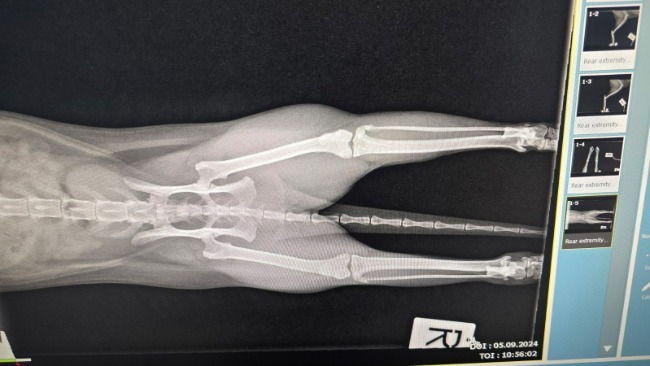

W obrazie RTG stawów skokowych uwidoczniono zmiany wytwórcze oraz powiększony obrys stawu, Kotka wykazuje dużą bolesność, która prawdopodobnie jest przyczyną problemów z wypróżnianiem. Niestety pojawiła się również gorączka.

Zalecone zostały konsultacje ortopedyczne. Udało się pilnie umówić cierpiące zwierzę do Przychodni Weterynaryjnej Pobłocki Miazga, gdzie wykonano kolejne badania RTG w kilku projekcjach, które potwierdziły obrzęk stawu.